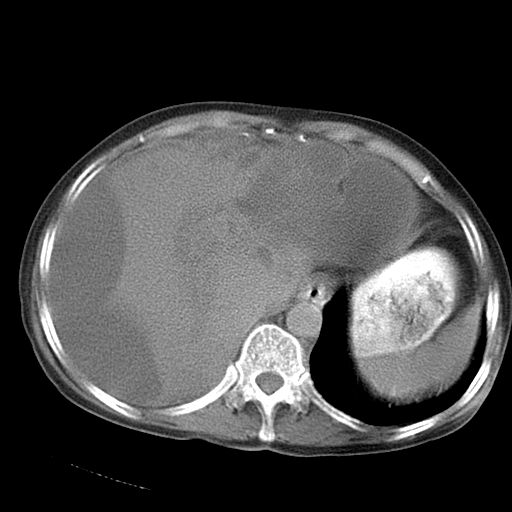

以下是引用dyqct在2006-12-7 21:08:00的发言:[br]考虑:1、肝内外胆管多发性结石伴肝左叶外侧段肝萎缩;[br] 2、右膈下多发脓肿;[br] 3、右侧少量胸腔积液、斜裂积液;[br] 4、左肾囊肿。

以下是引用jiazh在2006-12-7 20:37:00的发言:[br]肝脏周围半狐形低密度影,肝脏表面受压推移,考虑膈下脓肿可能性大;2、右侧胸腔积液

以下是引用拾荒者在2006-12-7 21:44:00的发言:[br]肝内外胆管多发结石,右膈下多发脓肿,右胸膜腔及叶间裂积液,左肾囊肿。[br] [br]